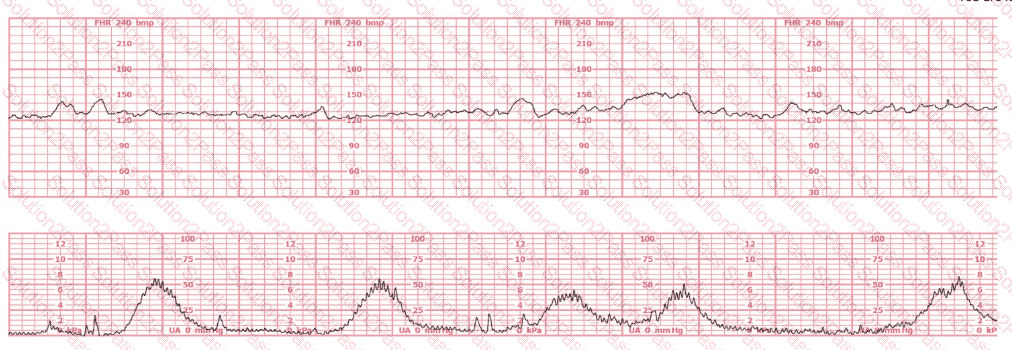

This fetal heart rate tracing represents:

The tracing shown is a: